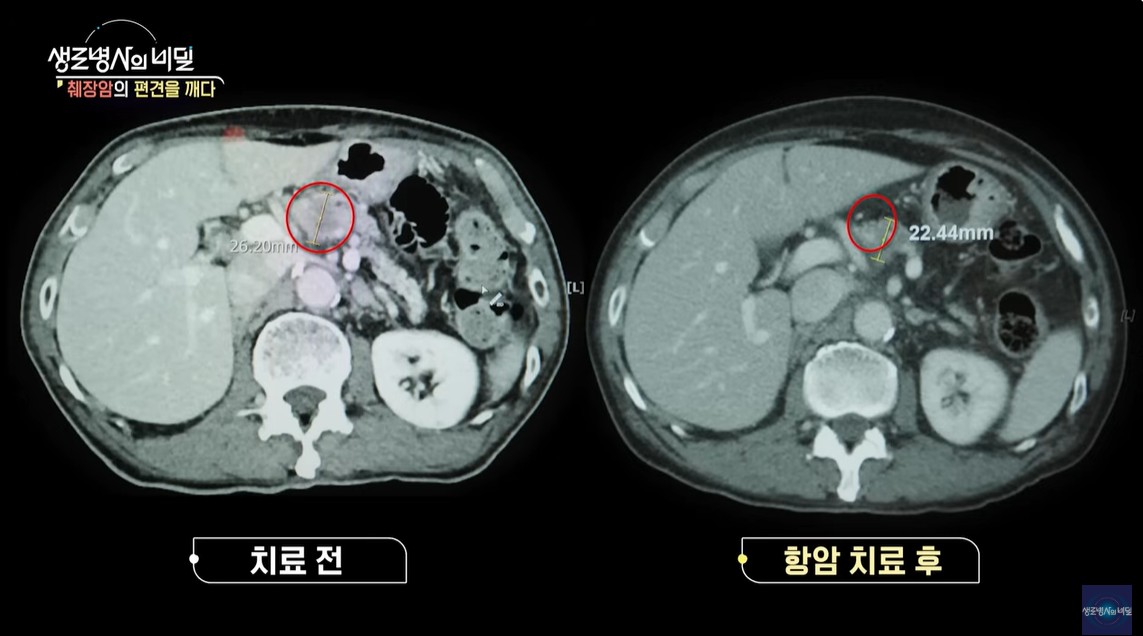

박대식 씨는 고령의 나이에 췌장암 진단을 받았고, 처음에는 항암과 방사선 치료로 예후를 개선했지만, 결국 수술 없이는 생존율을 높이기 어렵다는 결론에 도달했습니다.

종양 크기 감소와 체력, 전신 상태 평가 후 수술을 받기로 결정, 체력과 전신 상태를 체크하는 노인 포괄 평가를 거쳐 수술 결정했습니다.